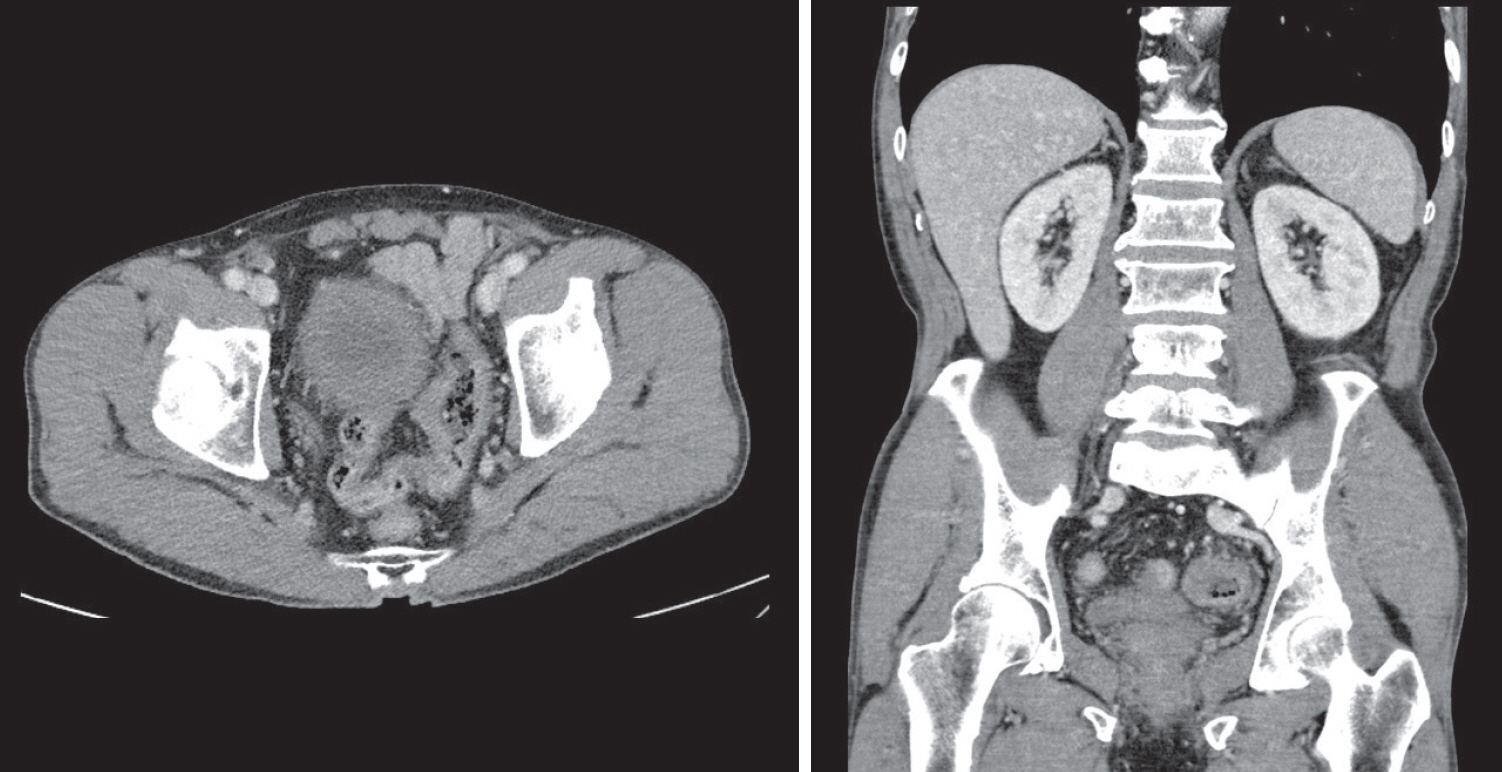

A 70-year-old male underwent sigmoidoscopy after a routine computed tomography (CT) examination, which showed thickening of the sigmoid wall (Fig. 1). Sigmoidoscopy revealed a colonic ulcer, and a biopsy was performed. The lesion was identified as a tubular adenoma; therefore, the patient was referred to the gastroenterology department for repeat biopsy and additional tests. The patient’s medical history included high blood pressure and alcoholic hepatitis. His social history showed that he drank 0.5-1.0 bottle of soju daily and was never a smoker. Information regarding his family history was excluded from the study. The patient had no gastrointestinal symptoms such as abdominal pain or diarrhea, and physical examination findings were unremarkable. Although the biopsy showed a tubular adenoma, the initial colonoscopy indicated that the gross margin of the ulcer was irregularly shaped (Fig. 2), raising suspicion for malignancy. Therefore, despite being asymptomatic, the patient was informed, and another colonoscopy was performed 2 months later. The follow-up examination revealed a scarred sigmoid ulcer located 30 cm from the anal verge, which seemed to have improved compared with the previous findings. Re-biopsy demonstrated features consistent with a simple ulcer (Fig. 3). Accordingly, we concluded that this was a benign colonic ulcer with an inflammatory and ischemic cause rather than cancer, and a follow-up CT scan was sche-duled 1 month later. At the follow-up visit 1 month later, the patient complained of abdominal discomfort after eating for a week, which had not occurred before. He denied having fever, chills, nausea, or vomiting. A subsequent abdominal CT scan showed an approximately 9-cm cavitary lesion abutting the sigmoid colon and urinary bladder dome in the small intestine (Fig. 4). This was accompanied by diffuse nodular omentomesenteric infiltration and peritoneal thickening with small ascites. Based on these findings, the patient was suspected to have a malignant tumor, such as scirrhous carcinoma, inflammatory bowel disease, peritoneal carcinomatosis, or peritonitis, and was referred to a surgeon for surgical treatment. The patient was hospitalized immediately. On admission, the patient complained of abdominal discomfort after eating, and mild generalized abdominal tenderness was noted on physical examination. He was hemodynamically stable. Laboratory testing revealed high white blood cell count of 11.45 × 103/μL (normal range, 4.0-10.0 × 103/μL) with a differential of 67.6% neutrophils (normal range, 38.0-75.0), normal hemoglobin of 16.1 g/dL (normal range, 13.0-17.0), normal platelet count of 151 × 103/μL (normal range, 150-400 × 103/μL), and slightly elevated C-reactive protein level of 7.69 mg/L (normal range, 0.0-5.0). Serum electrolyte and kidney function test results were normal. On the 3rd day of hospitalization, the patient underwent laparoscopic small bowel resection. Immunohistochemical analysis of the resected tissue showed positive staining for CD3, CD4, CD8, CD56, and CAM 5.2 (epithelial marker), and a negative staining for CD10, CD20, CD21, and CD30 (Fig. 5). Histopathological evaluation revealed infiltration by small- to medium-sized T-cell with prominent epitheliotropism, consistent with MEITL. The final diagnosis was MEITL, involving the sigmoid colon, urinary bladder, and peritoneum. Postoperatively, the patient developed persistent ileus with progressive ab-dominal distension and loss of bowel passage, necessitating a second emergency surgery on the 20th day of hospitalization. On the 25th day of hospitalization, the Hemovac drainage became purulent, blood pressure decreased, and the patient went into shock; therefore, a third emergency surgery was performed under the suspicion of bowel perforation. On the 45th day of hospitalization, the patient died of refractory septic shock, presumed to be a complication of intestinal perforation.

Figure 4.

Subsequent abdominal computed tomography (CT) showing an approximately 9-cm cavitary lesion in the small intestine, abutting the sigmoid colon and urinary bladder dome.